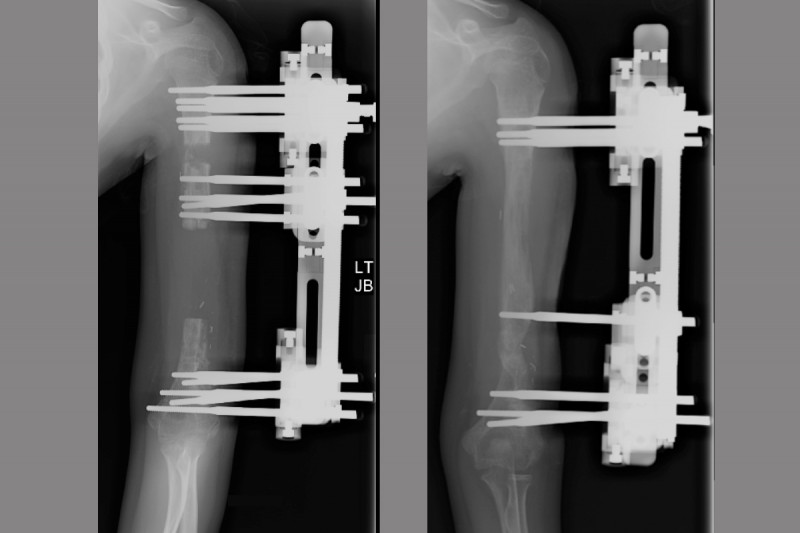

So what is the solution you may ask? Well it is arm lengthening

So what is the solution you may ask? Well it is arm lengthening